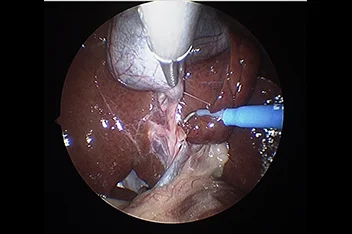

기존의 개복수술은 충분한 노출을 위하여 복부의 피부와 복벽 근육을 길게 절개해야 합니다.

하지만 복강경을 이용하면 보통 3mm-10mm 직경의 포트를 통해 복강 내에 이산화탄소를 주입하여 공간을 만들고,

카메라를 통해 더 뚜렷하게 시각화할 수 있고 지혈 기구를 통해 장기들을 안전하게 분리하여 절제할 수 있습니다.

복강경의 경우 대형견에서 그 장점이 뚜렷하며 현재는 소형견, 고양이에서도 이러한 장점 때문에 최소 침습 수술을 진행하게 됩니다.

본원에서는 간단한 중성화나 조직생검 외에도 부신절제술, 담낭절제술, 신장절제술, 비장절제술, 간엽절제술 등을 포함한

고난도 수술도 실시합니다.

복강경신장절제술

복강경부신절제술

복강경담낭절제술